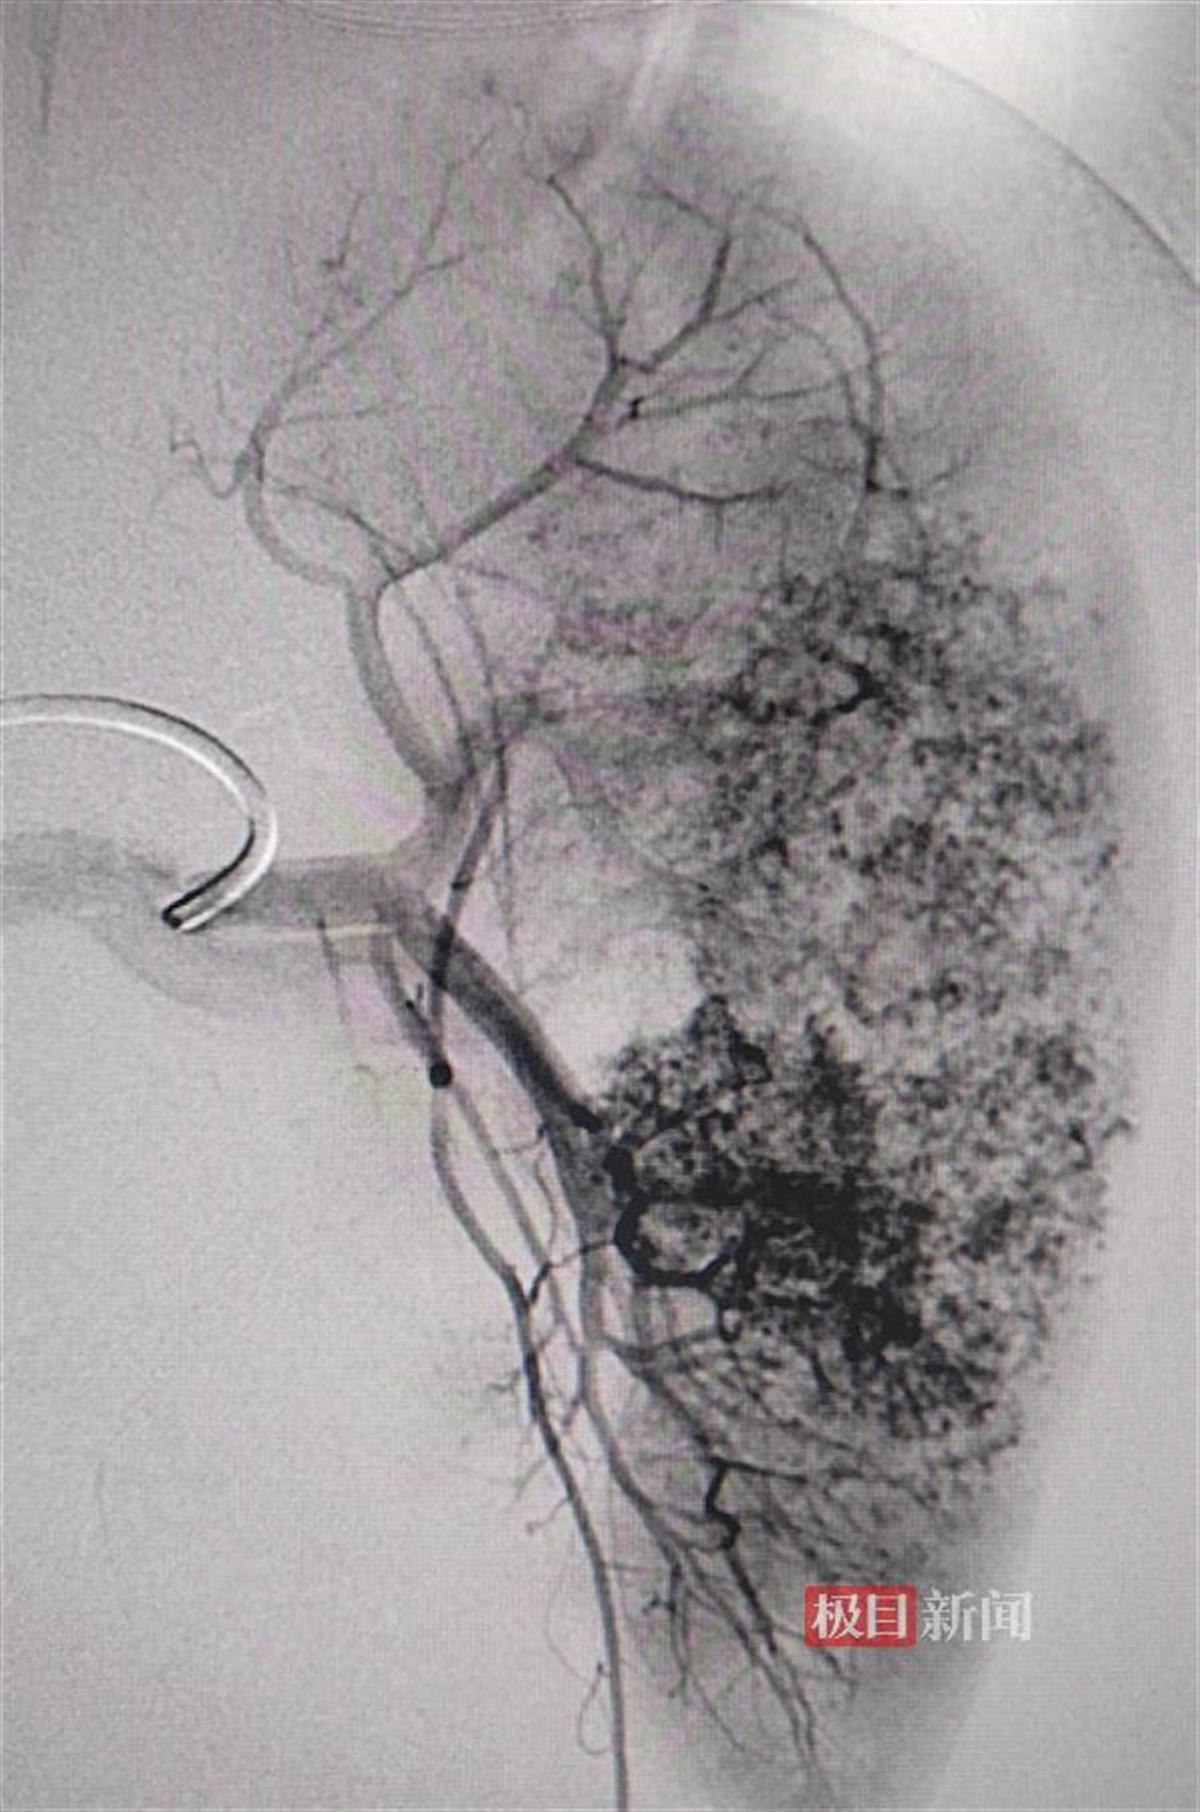

治疗前脾脏动脉造影

当日清晨,康康被推入手术室。术中,介入放射科主任刘新献、郭严延医生从孩子的右侧股动脉穿刺,将造影导管送到脾动脉主干,在造影剂的帮助下“锁定”出血的分支动脉,随后将微导管置入、实施栓塞,成功帮康康止血保脾。